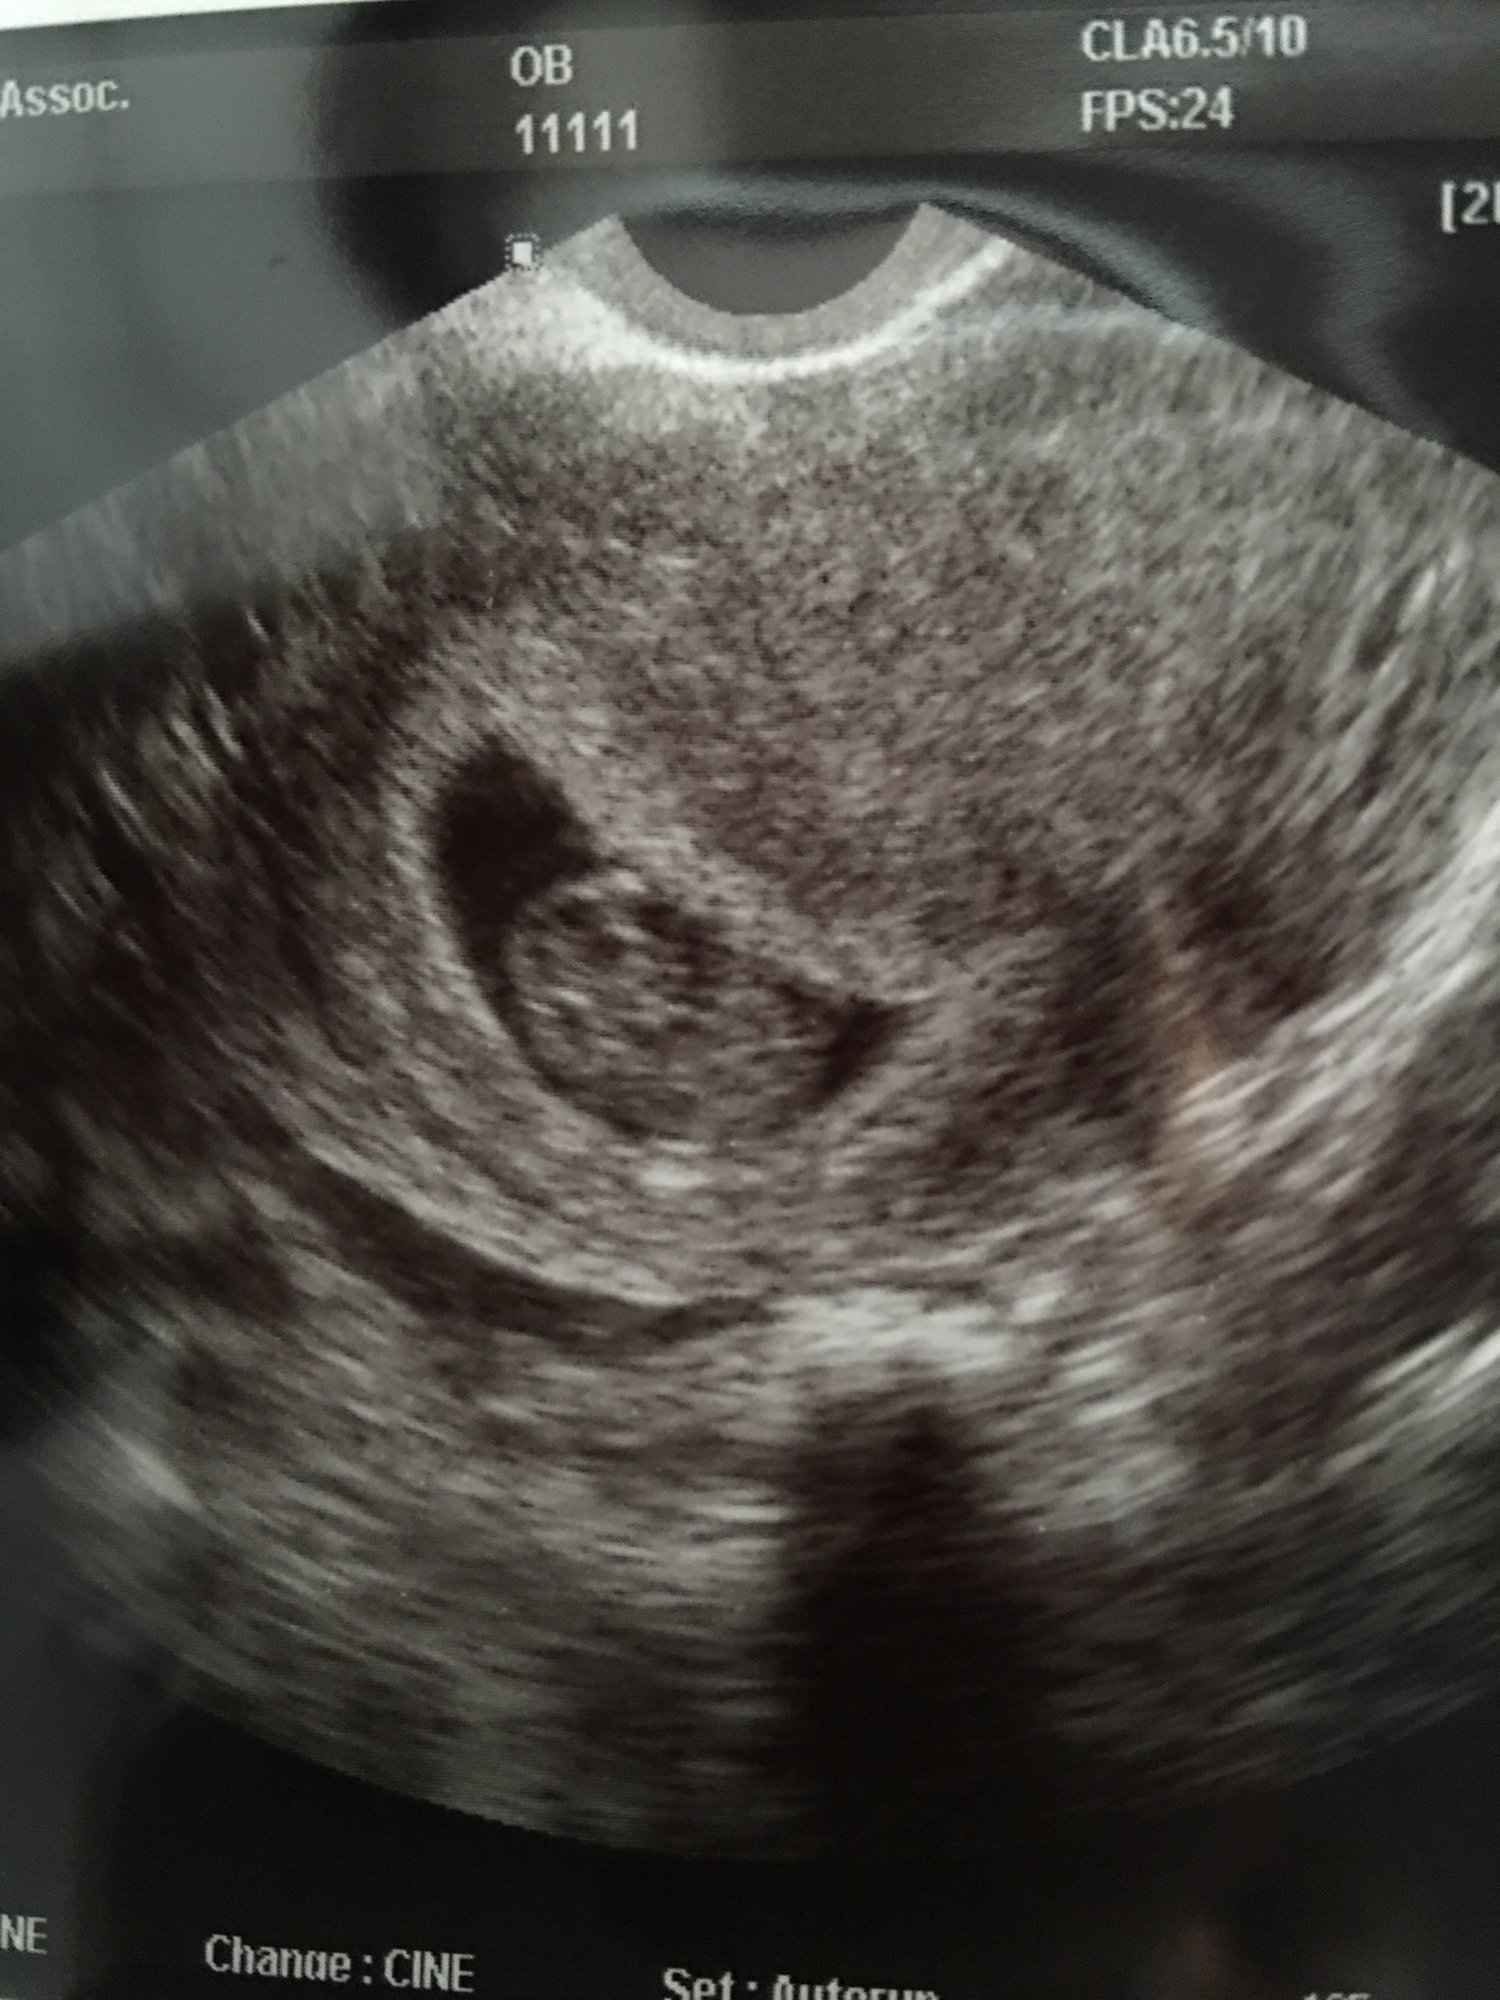

Yay! Just had my first ultrasound and therere's a baby and a beating heart in the sac. I was too in shock to remember what she said the heart rate was. After my last blighted ovum I'm so relieved! I thought I'd be 6w6 but baby is measuring 6w2. Trying hard not to worry even though doc says she's not. 2 weeks and 1 day till I get to see her again with a FU ultrasound.